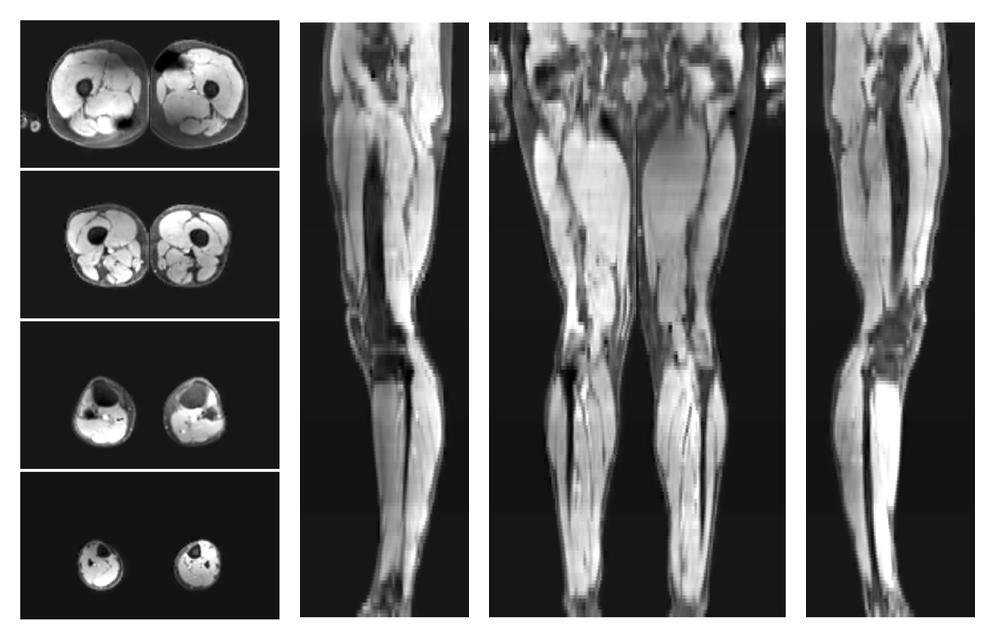

• Mean diffusivity

IVIM corrected whole leg muscle mean diffusivity obtained from diffusion tensor imaging.